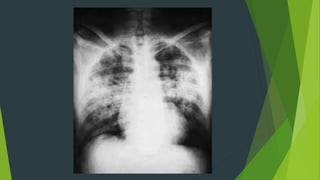

Hội chứng phế bào

Định nghĩa:

Gồm các dấu hiệu hình ảnh thể

hiện có dịch hoặc tế bào lành hay

ác tính trong lòng phế nang

Chẩn đoán HCPB khi có 2 trong 7 triệu

chứng điển hình

7 triệu chứng điển hình

1. Nốt mờ phế nang

2. Bờ tổn thương mờ (nếu tựa lên rãnh liên thùy thì bờ rõ)

3. Có xu hướng tập trung

4. Đám mờ hình tam giác, dạng thùy hay phân thùy, không

đồng nhất

5. Có thể có mờ hình cánh bướm

6. Hình nhánh phế quản khí

7. Lan rộng và biến mất nhanh (dưới 48h)